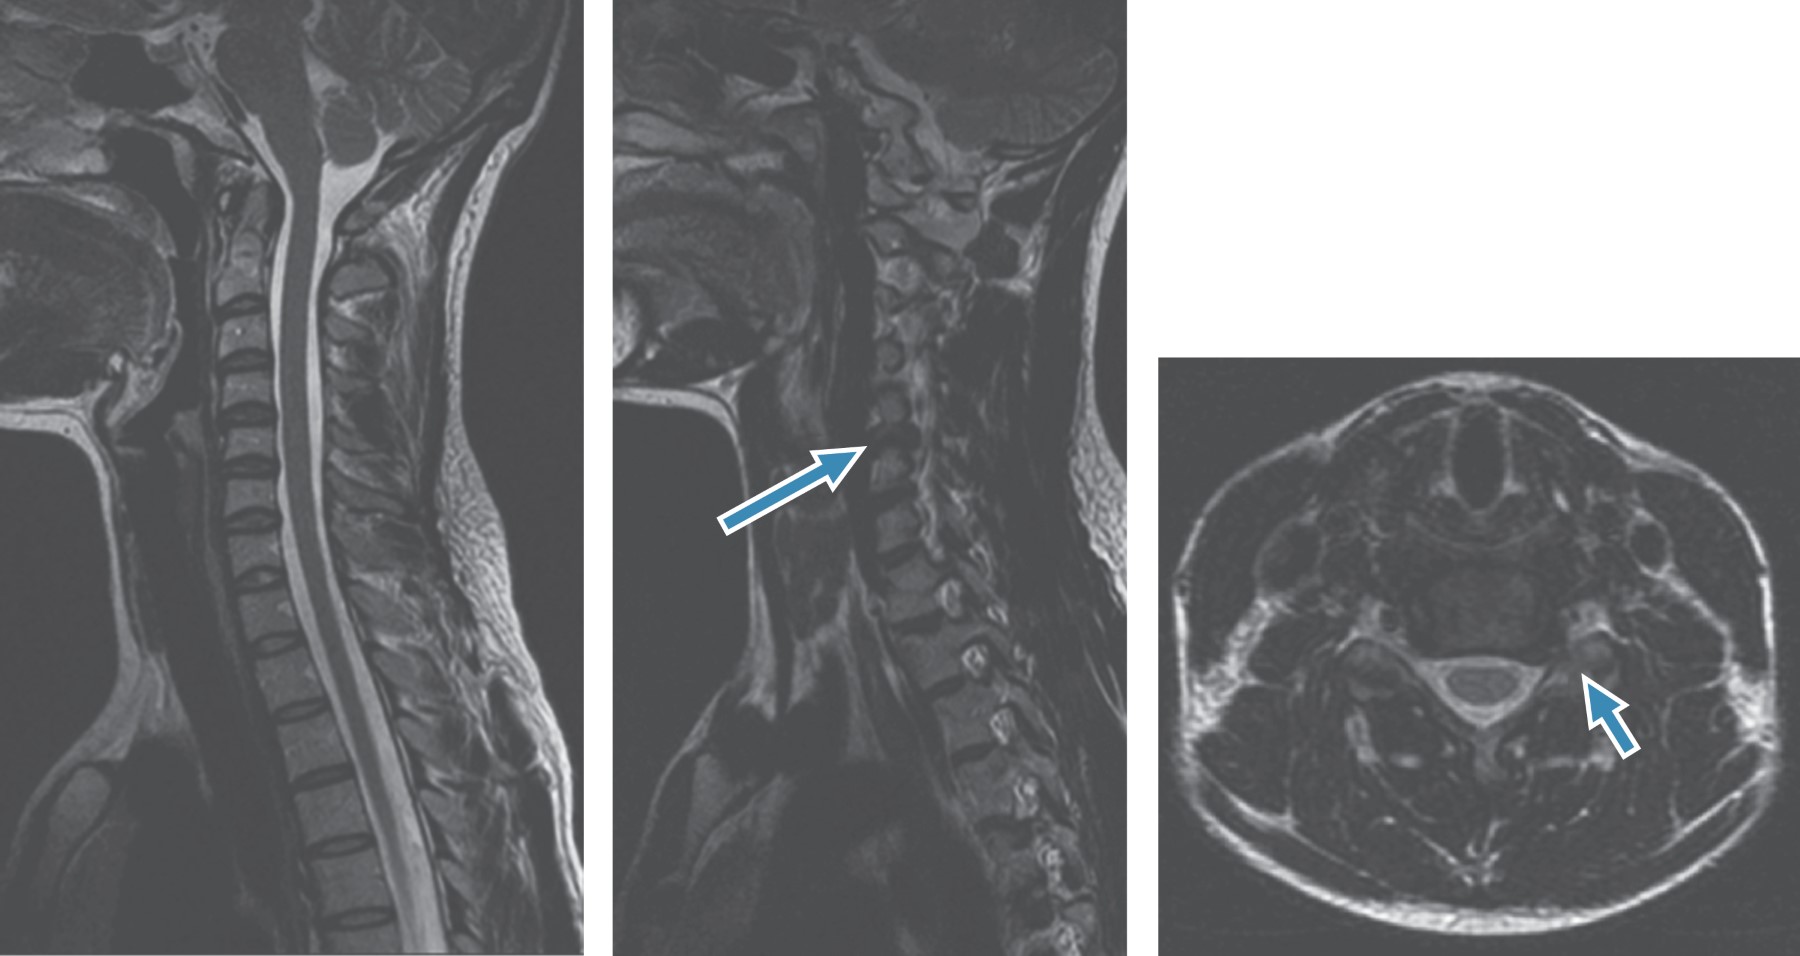

In June 2011 she was referred for an orthopedic review. In July the same year she was diagnosed with a C5-6 left foraminal herniation and started non-operative treatment with physiotherapy. The herniation was compressing left C6 nerve root as seen on MRI (Figures 1 and 2). During the treatment she stated that just mild relief was achieved during neck traction, worsening immediately after. She did seek spinal specialist opinion in August 2011, suffering from an intensive neck and left arm pain with sensitivity loss and transient motor deficit. The motor deficit would occur during her practice when she raised her arm toward the head for protection. Every time the guard was set, a sudden pain would appear with loss of power in the arm and hand, dropping both and dismounting her protection. This deficit would put her in further danger from a blow struck from her opponent to the head.